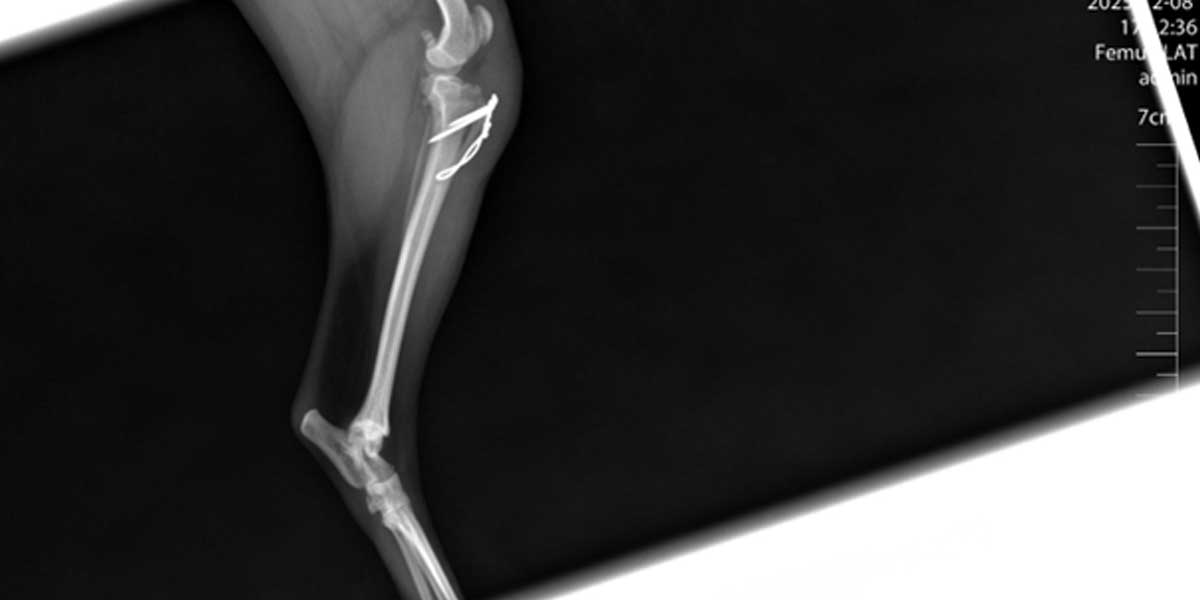

Tijekom operacije ispravljaju se koštane i mekotkivne nepravilnosti koljena.

Zahvat može uključivati produbljivanje žljeba koljena (trohleoplastika) i prilagodbu položaja tetiva (TTT).

U najtežim slučajevima potrebna je korektivna osteotomija.